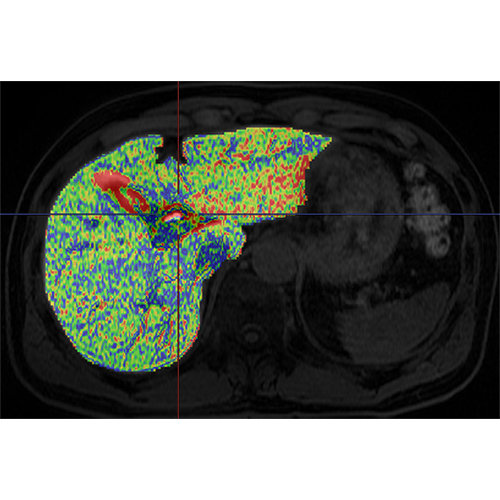

View X-Ray CT & MRI Scans Fast and Easily

Designed for surgeons, Pro Surgical 3D makes it easy to view patient scans quickly. Pro Surgical 3D facilitates the optimal 3D treatment and assessment workflows based on X-ray CT and MRI scans – and best of all, it’s FREE!

High-quality and fast 3D reconstruction and 3D rendering

Performs 3D reconstruction and volume rendering.

Multi-planar slicing.